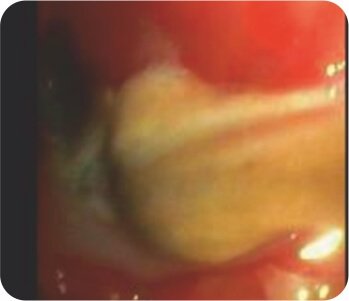

Bronchoscopy – Pus oozing from left upper lobe bronchus

Bronchoscopy – Mass/ Clot occluding the left upper lobe bronchus